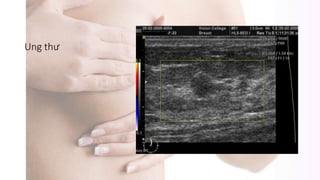

Siêu âm

Ung thư